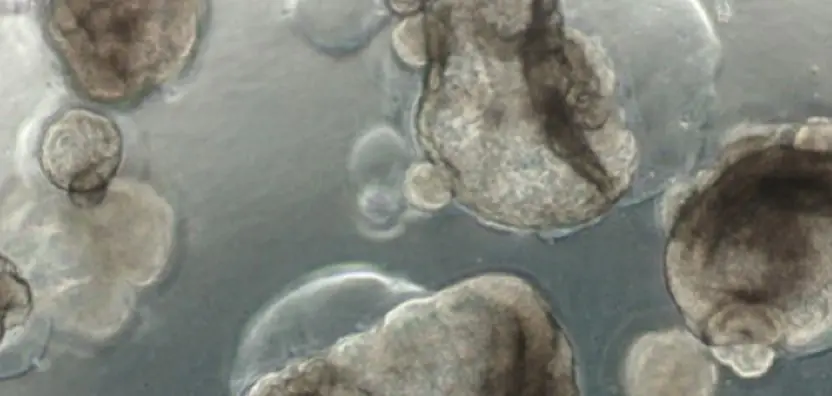

Traditional microscopy methods often require fluorescent labeling to analyze cellular structures, which can be time-consuming and invasive. In contrast, our HT-X1 system allows for high-resolution visualization of cellular morphology without the need for any labeling, offering a clear advantage in live-cell imaging. To validate this capability, we conducted an organoid-based analysis using intestinal organoids. Among various organoid types, intestinal organoids are known to closely replicate the functional structure of the...

Holotomography is a groundbreaking technology that enables high-resolution observation of dynamic changes in cells without fluorescent staining, while preserving their natural state. This technique does not interfere with the physiological changes of cells, allowing for real-time analysis of their internal structures and functions over extended periods. LEE (SNU): "Our research team utilized holotomography to observe various dynamic changes, such as cell division, migration, and death, in mouse intestinal organoids over...